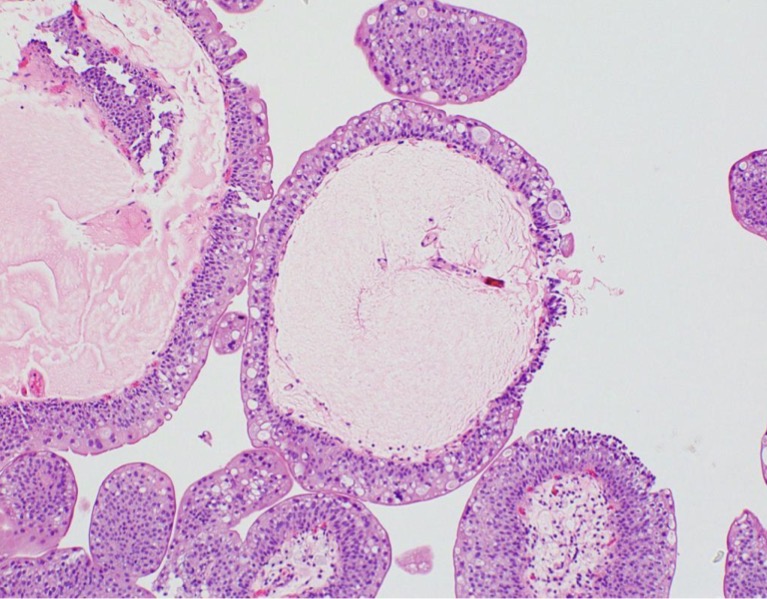

A- identify

B- describe

C- originate from ?

A- Urothelial papilloma

B- Papillary fronds with fibrovascular cores are lined by normal appearing urothelium

C- from benign epithelial tissue